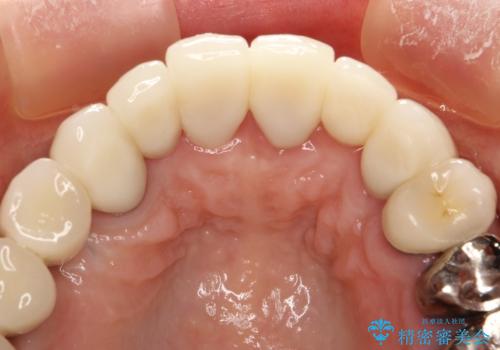

前歯の低クオリティな治療の実態 妥協無い治療で根本からやり治す

- 歯周外科・再根管治療後、クラウンを製作する。

かぶせ物の種類:PFZ standard